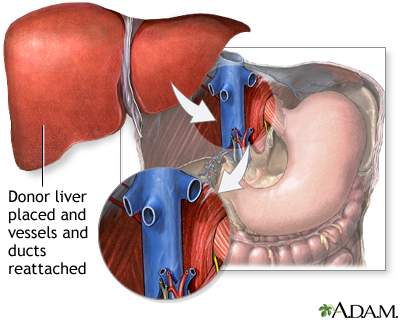

The new liver is removed from the donor through a surgical cut in the upper abdomen. It is placed into the person who needs the liver (called the recipient) and attached to the blood vessels and bile ducts. The operation may take up to 12 hours. The recipient will often need a large amount of blood through a transfusion.